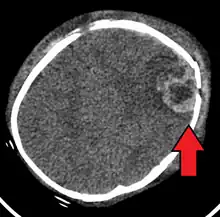

| An intraparenchymal bleed with overlying skull fracture from shaken baby syndrome | |